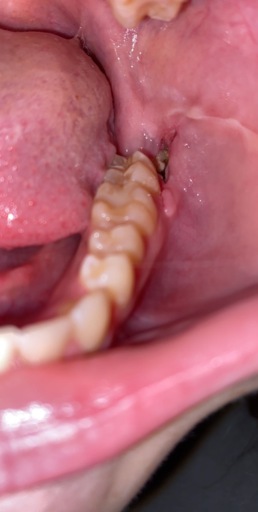

I had my back left wisdom tooth removed 72 hours ago and I can feel and see a large grey soft lump (size of a tooth). It's definitely very different to my first wisdom tooth removal which was plain sailing! I've followed all instructions with paracetomol and ibrorprofen and waited 24 hours until gentle salt water washes and gentle Cordosyl rinses. It extends whenever I do my rinses (feels like a lot of loose skin/tissue?!?). Any help would be greatly appreciated. I'm not in lots of pain but discomfort and the odour and taste in my mouth is deeply unpleasant.

Without a photo of the area it is hard to see exactly where the tissue is and to where it extends. Like any other area that bleeds on our skin, a scab is formed. The mouth is no different when new tissue is forming. It is best to check with the dentist or surgeon that performed the extraction to see if sutures were placed and if any collagen may have been added. This could be what is extending and not your tissue itself. The foul odor could be produced from decomposing food in the socket that is not being properly cleaned. Be sure you are rinsing with warm salt water several times a day to remove debris and taking prescriptions as written. Discomfort 72 hours after an extraction is normal, it should continue to get better everyday.